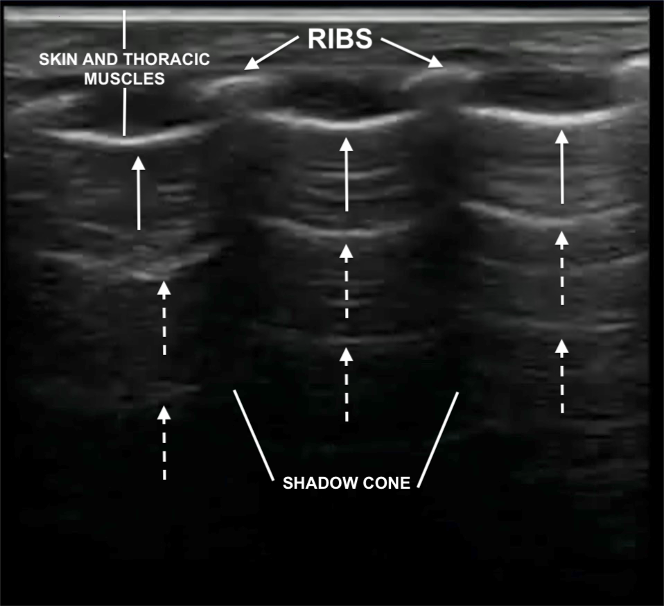

- Ribs (may or not have a shadow cone, if ossified or cartilaginous, respectively)

Ultrasound characteristics of normal neonatal lung. Pleural line (white arrows) and A‐lines (dashed white arrows)

As mentioned above, ultrasound findings of a normal lung, from top to bottom are:

- Skin and thoracic muscles

- Ribs, only in longitudinal not in transverse scanning. Ribs may or not have a shadow cone, if ossified or cartilaginous, respectively.

- Pleural line: in normal lung is thin, smooth, regular and hyperechoic.

- A-lines: below the pleural line, there are reverberation artifacts called A‐lines. They are equidistant hyperechoic parallel lines, caused by multiple reflections of the pleural line. The A-lines gradually fade as they move towards the bottom of the screen, where they ultimately disappear.

- No or few B lines. Particularly in the transitional period, single or non-confluent B‐lines are normal findings.